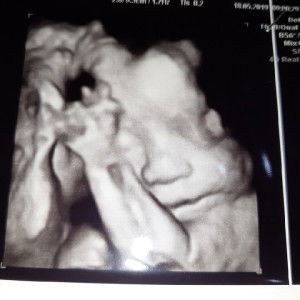

Bun ank ku bru 12hari. Asi ku kurng lncar. Dan si baby kuat bngt mnum. Jd aq tmbhin sufor. Itu bgus gk si bwt baby